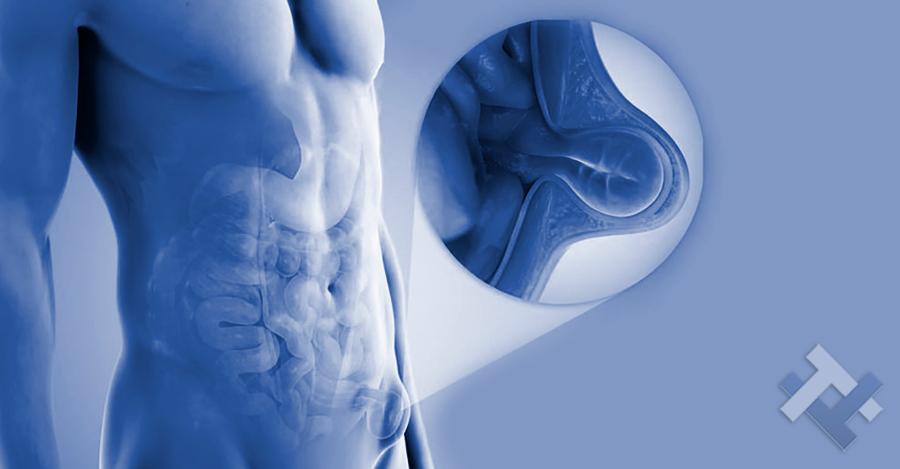

Κήλες - Κοιλιοκήλες:

Κήλες - Κοιλιοκήλες:

Ο Γενικός Χειρουργός Λιάγκος Γεώργιος MD PhD εκτελεί τις επεμβάσεις Λαπαροσκοπικά, Ενδοσκοπικά, Ανοιχτά Ελάχιστα Επεμβατικά και με Laser. Η θεραπεία εξατομικεύεται σε κάθε ασθενή ανάλογα με τις ανάγκες του. Αναλαμβάνει περιπτώσεις όπως κήλες και κοιλιοκήλες (αντιμετώπιση βουβωνοκήλης, αντιμετώπιση ομφαλοκήλης, θεραπεία επιγαστρικής κήλης, κήλη των αθλητών (Σύνδρομο κοιλιακών προσαγωγών), αντιμετώπιση μετεγχειρητικής κήλης, θεραπεία Μηροκήλης), πέτρες στη χοληδόχο κύστη, λαπαροσκοπική χολοκυστεκτομή, αντιμετώπιση Κύστη Κόκκυγος με λέιζερ (laser), παθήσεις πρωκτού, χειρουργική laser σύγχρονων κυκλικών ινών (αιμορροΐδες αντιμετώπιση, θεραπεία αιμορροϊδων με laser (LHP), αφαίρεση αιμορροΐδων με υπερήχους (HALL-RAR), χωρίς Χειρουργείο με ελαστικούς δακτυλίους (Τεχνική BARON-RBL), θεραπεία ραγάδας πρωκτού (Ραγάδα δακτυλίου), θεραπεία περιεδρικού συριγγίου, θεραπεία περιεδρικού αποστήματος, κονδυλώματα πρωκτού Θεραπεία, δερματικό ράκος (Skin tag) εκτομή, αντιμετώπιση Kνησμού, καρκίνος πρωκτού θεραπεία), παθήσεις Δέρματος, χειρουργική με laser CO2, αφαίρεση μορφωμάτων δέρματος - βιοψίες, αφαίρεση ελιάς (Σπίλου), σμηγματογόνος κύστης θεραπεία, αφαίρεση λιπώματος, είσφρυση όνυχος χειρουργείο, καρκίνος δέρματος θεραπεία, οξεία σκωληκοειδίτιδα, παθήσεις Λεπτού και Παχέος Εντέρου, ειλεός λεπτού εντέρου, εκκολπωμάτωση (Εκκολπωματίτιδα) σιγμοειδούς, καρκίνος παχέος εντέου, κολοστομίες, port χημειοθεραπείας κ.α.

Ο Γενικός Χειρουργός Λιάγκος Γεώργιος MD PhD εκτελεί τις επεμβάσεις Λαπαροσκοπικά, Ενδοσκοπικά, Ανοιχτά Ελάχιστα Επεμβατικά και με Laser. Η θεραπεία εξατομικεύεται σε κάθε ασθενή ανάλογα με τις ανάγκες του. Αναλαμβάνει περιπτώσεις όπως κήλες και κοιλιοκήλες (αντιμετώπιση βουβωνοκήλης, αντιμετώπιση ομφαλοκήλης, θεραπεία επιγαστρικής κήλης, κήλη των αθλητών (Σύνδρομο κοιλιακών προσαγωγών), αντιμετώπιση μετεγχειρητικής κήλης, θεραπεία Μηροκήλης), πέτρες στη χοληδόχο κύστη, λαπαροσκοπική χολοκυστεκτομή, αντιμετώπιση Κύστη Κόκκυγος με λέιζερ (laser), παθήσεις πρωκτού, χειρουργική laser σύγχρονων κυκλικών ινών (αιμορροΐδες αντιμετώπιση, θεραπεία αιμορροϊδων με laser (LHP), αφαίρεση αιμορροΐδων με υπερήχους (HALL-RAR), χωρίς Χειρουργείο με ελαστικούς δακτυλίους (Τεχνική BARON-RBL), θεραπεία ραγάδας πρωκτού (Ραγάδα δακτυλίου), θεραπεία περιεδρικού συριγγίου, θεραπεία περιεδρικού αποστήματος, κονδυλώματα πρωκτού Θεραπεία, δερματικό ράκος (Skin tag) εκτομή, αντιμετώπιση Kνησμού, καρκίνος πρωκτού θεραπεία), παθήσεις Δέρματος, χειρουργική με laser CO2, αφαίρεση μορφωμάτων δέρματος - βιοψίες, αφαίρεση ελιάς (Σπίλου), σμηγματογόνος κύστης θεραπεία, αφαίρεση λιπώματος, είσφρυση όνυχος χειρουργείο, καρκίνος δέρματος θεραπεία, οξεία σκωληκοειδίτιδα, παθήσεις Λεπτού και Παχέος Εντέρου, ειλεός λεπτού εντέρου, εκκολπωμάτωση (Εκκολπωματίτιδα) σιγμοειδούς, καρκίνος παχέος εντέου, κολοστομίες, port χημειοθεραπείας κ.α.